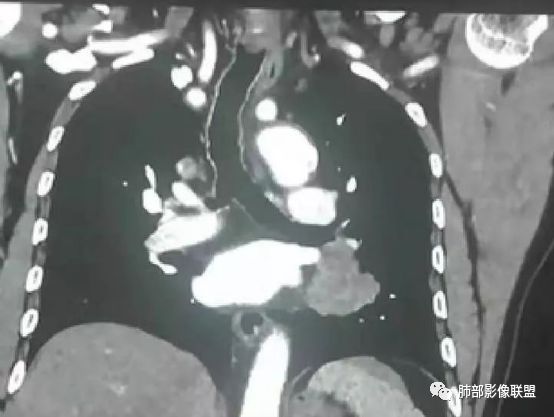

患者,男 ,66岁, “左肺占位”收住院。CEA   5.23 轻度增高

平扫 动脉期 静脉期  40HU、48HU、57HU

患者老年男性,“左肺占位”收入住院。查CEA轻度升高。胸部CT:左肺肺门占位并左肺下叶阻塞性,远端肺组织膨胀不全,增强可见轻度强化,内似见低密度灶。双肺多发类圆形结节,以左肺上叶尖后段为大,内可见部分钙化,边缘光滑、清楚。综合考虑恶性病变,鳞癌并转移可能大,鉴别腺癌、结核。

胸CT:左下叶内前基底段肿块,支气管堵塞,强化弱,延迟强化,两肺多处结节,右上肺门淋巴结大。常规考虑:肺癌可能 ,肺内小结节,转移?鉴别:错构瘤,TB等。

左肺下叶占位,左肺下叶前内支气管阻塞可疑(缺乏薄层),病灶有膨胀性,远端较内侧细,增强病灶强化不明显——乏血供病灶,病灶沿支气管生长,考虑恶性病变,左肺上叶可见小结节病灶,边缘光滑清晰,考虑转移瘤,综上所述考虑恶性病变,左肺下叶小细胞类癌可能,左肺上叶转移。

1.定位:左肺块影同时累及下舌段及下叶内基底段且相互延续。病灶跨叶,或存在叶裂发育异常,或者说就是病灶的肺门蔓延。

2.病灶前上部分与舌段支气管相关且形成阻塞。

4.增强扫描左肺门区块影轻度强化,强化程度轻于舌段周围不张肺组织。

6.分析:男性患者,左肺门区块状影,支气管阻塞,强化不显著,未见淋巴结肿大,更多见于肺鳞癌。难以解释的是下肺病灶的生长方式。

沿肺门或是叶裂缺损孤立发生且蔓延,转移性腺癌似乎可以解释,但占据较大支气管腔就属罕见了。